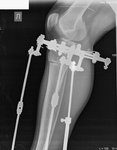

Перед крутками!

IMG-20180424-WA0018.jpg

IMG-20180424-WA0019.jpg